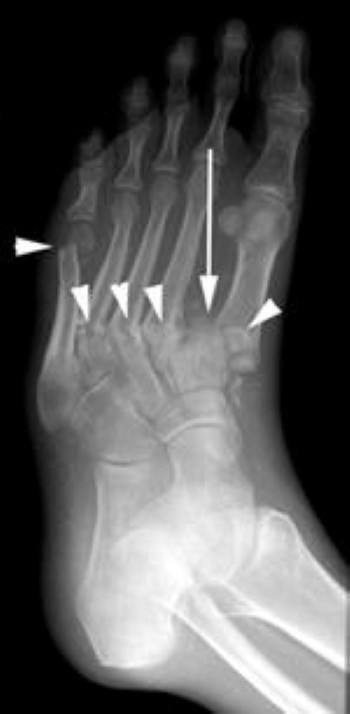

fractures and dislocation of metatarsals

The patient shown in the X-ray had noticed swelling of the foot for approximately 3 weeks without any known injury. The X-ray shows several fractures (arrowheads) and a dislocation of the first metatarsal (arrow). Such a severe injury in patients without diabetes would be seen only after a high-energy trauma.